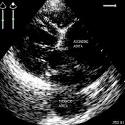

Aneurysm of the thoracic and abdominal aorta in a patient aged 67 years detected incidentally in pre-anesthesia consultation

Zine el Abidine Benali, Hatim Abdedaim

PAMJ. 2013; 16: 155. Published 22 December 2013